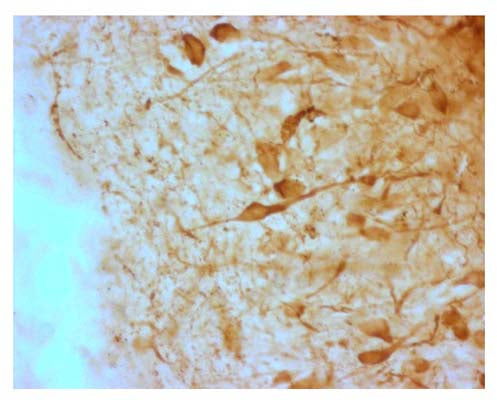

The 4% PFA fixed, frozen cryostat section of the sheep hypothalamus was incubated in guinea pig polyclonal antibodies to the mouse AGRP protein at the dilution of 1:1000 overnight followed by incubation with biotinylated secondary antibodies. Cell bodies and nerve terminals in the sheep brain are intensely stained. This figure shows staining of cells when no pre-absorption is performed.

IHC, frozen, PFA fixed material. Not yet tested on paraffin embedded tissue sections. A concentration of 1:1000 to 1:2000 is recommended for IHC with overnight incubations. Permeabilization suggested is 0.1% triton X-100 in blocking buffer. IHC performed in sheep brain (hypothalamus) demonstrates intense staining of cells and terminals. No staining is evident when the primary antibody is pre-absorbed with 0.5 mg/mL of AGRP. In rodents such as rat cell terminal staining is most typically observed without cell body staining. Biosensis recommends optimal dilutions/concentrations should be determined by the end user.